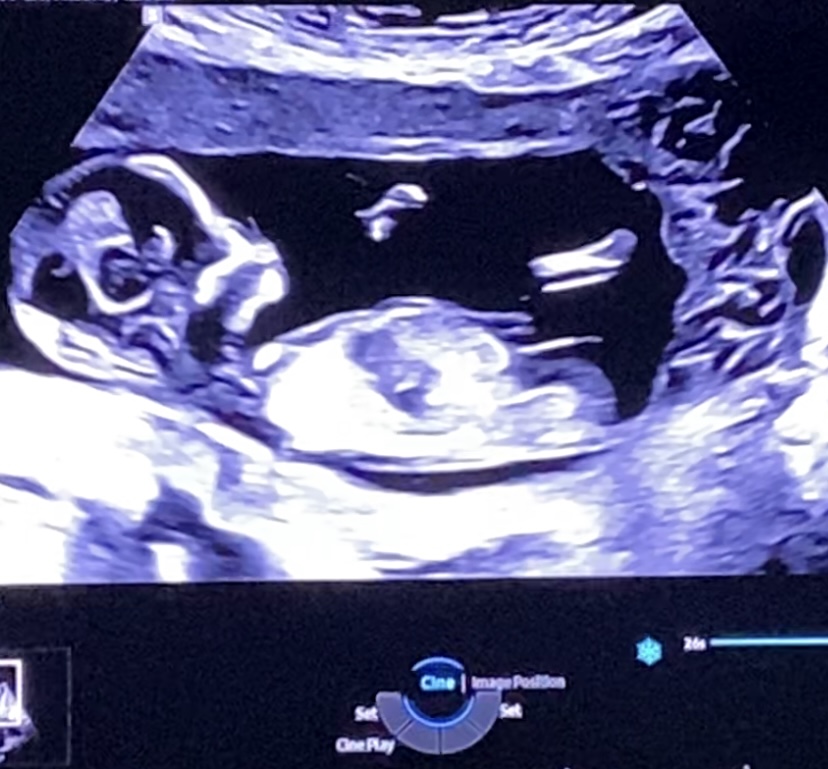

Tricky NUB 13+1 weeks? Long NUB but some stacking?

I had a scan yesterday (13+1 weeks!). During the scan I was convinced I saw long somewhat flat, but also a stacked nub (I saw a shadow in the background), but the tech said it was the stacking was the umbilical cord. The tech said she saw a flat NUB that I is why she was leaning more towards girl.

I posted my scans online and got mostly boy guesses (some girl because of the "flat" NUB) but I was wondering if it's still possible it might be a girl? That the "stacked thing" is something else??? (Already got 3 boys so a girl would be so welcome!)